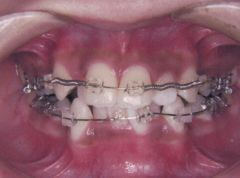

ステップ7.治療開始

装置装着前

装置装着後

※治療期間について

元の歯ならびの状態にもよりますが、

通常約1年から2年ぐらいです。